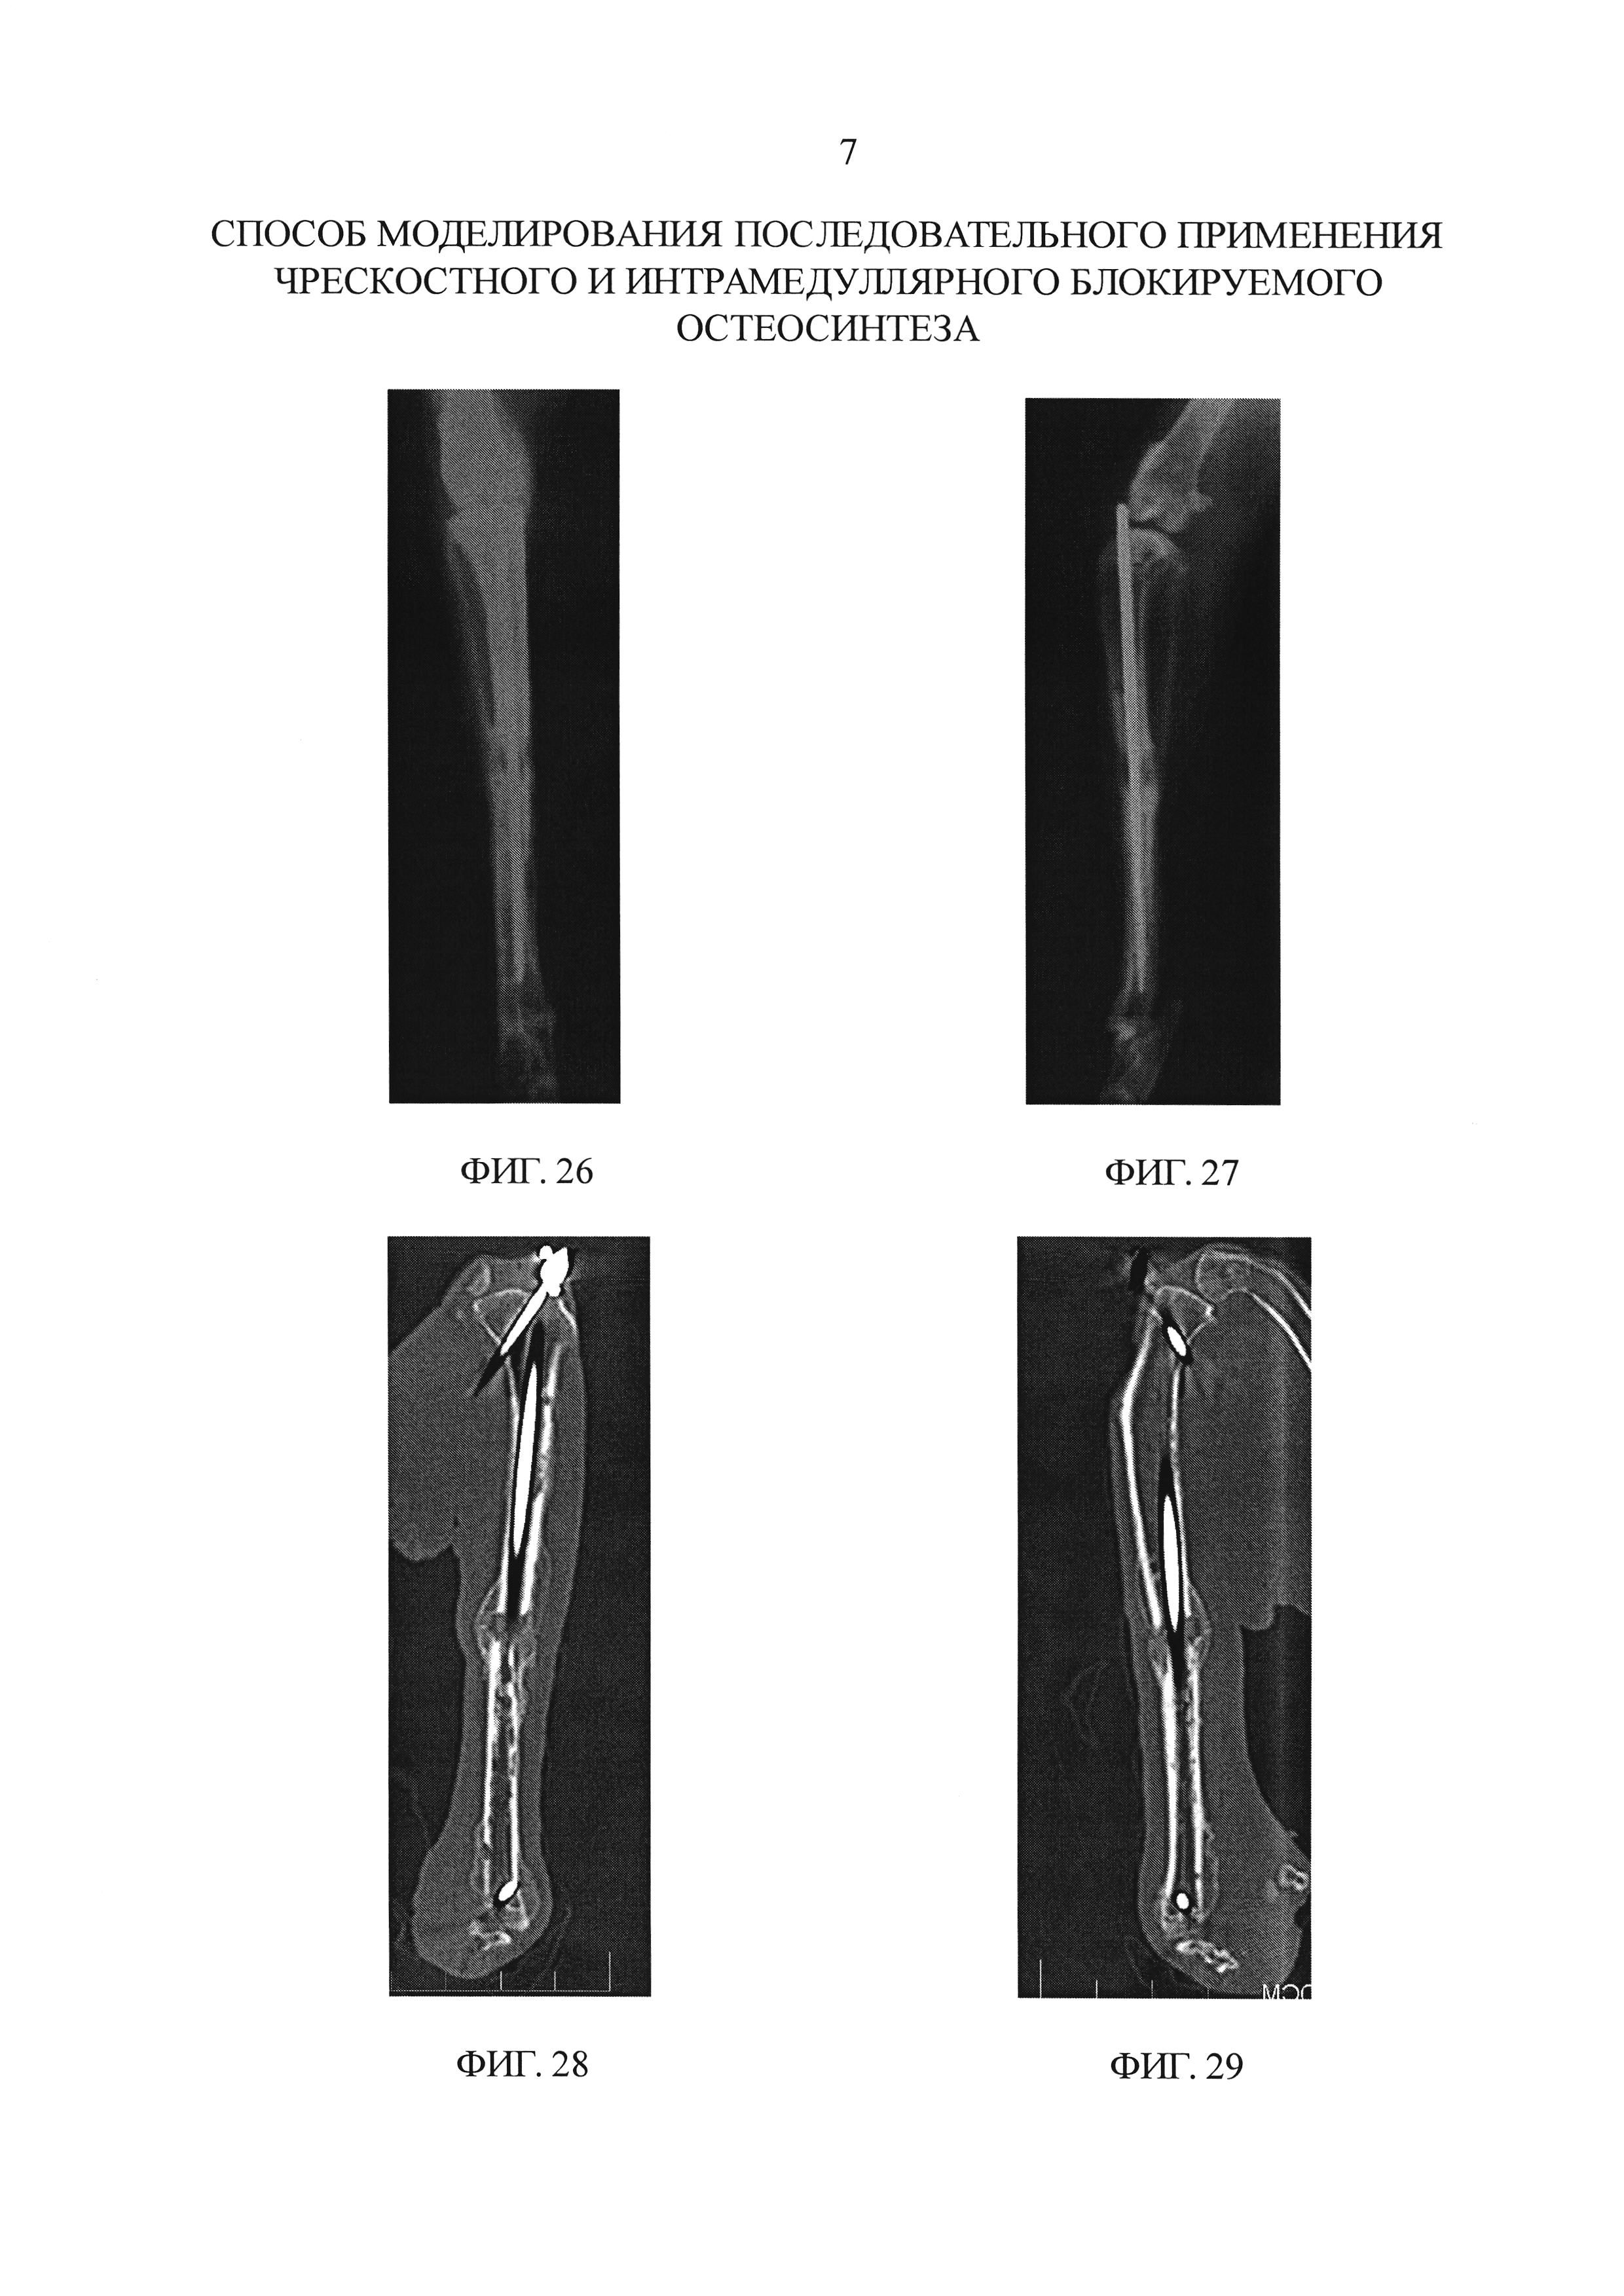

[Лечение переломов средне-дистального отдела диафиза плечевой кости, связанных с параличом лучевого нерва, методом малоинвазивного остеосинтеза с помощью винтовых гвоздей]

Задача: Цель исследования.

Изучить хирургическое лечение переломов средне-дистального отдела диафиза плечевой кости, связанное с параличом лучевого нерва, с помощью минимально инвазивной техники остеосинтеза гвоздями.

Методы: Тридцать шесть пациентов лечили переломы средне-дистального отдела диафиза плечевой кости, связанные с параличом лучевого нерва, с января 2004 г. по январь 2008 г. Было 28 мужчин и 8 женщин в возрасте от 20 до 58 лет, в среднем 36,5 лет. Старый. Причины травм: механические травмы 18 случаев, дорожно-транспортные происшествия 8 случаев, несчастные случаи травмы 10 случаев, переломы во всех случаях закрытые.Согласно классификации AO / ASIF, корпуса типа A1 5, корпуса типа A2 7, корпуса типа B1 8, корпуса типа B2 7, корпуса типа B3 5, корпуса типа C3 4. Выполнен небольшой боковой разрез, расположенный до перелома. После обследования лучевого нерва переломы уменьшились. Путем небольшого бокового разреза акромиона отделили дельтовидную мышцу.

В задней макронодульной прорези антеградное отверстие рассверлили сверлом для костномозговой полости и выбрали подходящий винтовой гвоздь, ввинченный в костномозговую полость дистально.Вдоль паза вставлялись фиксаторы для завершения фиксации. Регистрировали послеоперационное осложнение, время заживления перелома, время восстановления функции лучевого нерва, движения плеча и локтя.

Полученные результаты: Разрез во всех случаях зажил на I стадии. Пациенты наблюдались в течение 9-36 недель, в среднем 18,5 недель. При рентгенологическом исследовании переломы зажили через 12-16 недель (в среднем 15.6 недель). Функция лучевого нерва полностью восстановилась через 12-36 недель после операции (в среднем 17,8 недели). Отведение плеча составляет 150-170 градусов, в среднем 160 градусов; движение локтевого сустава составляло 130-140 градусов, в среднем 135 градусов. Для оценки функции плечевого сустава использовался метод ASES, в 20 случаях был получен отличный результат, в 12 — хороший и в 4 — плохой.

А по методу HSS в 36 случаях функции локтевого сустава отличный результат.

Заключение: Эффективно хирургическое лечение переломов средне-дистального отдела диафиза плечевой кости, связанное с параличом лучевого нерва, с применением минимально инвазивной техники остеосинтеза с помощью винтовых гвоздей.